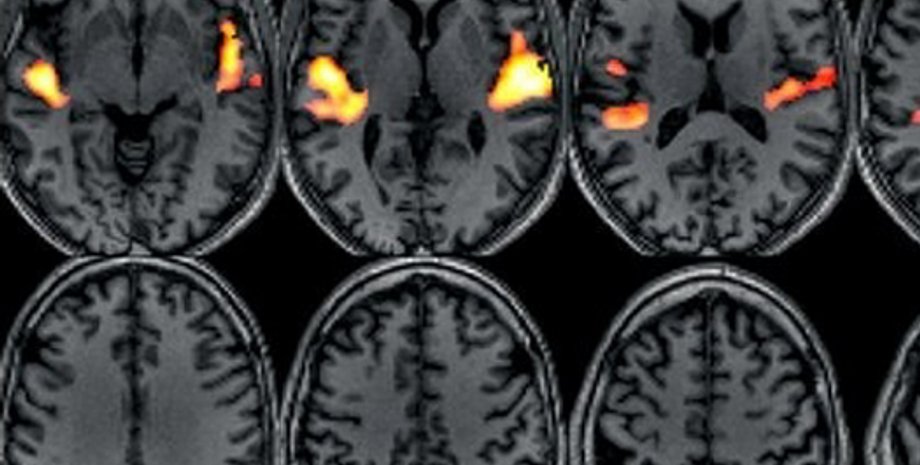

Главным инструментом в исследованиях профессора является функциональный магнитно-резонансный томограф; сам профессор специализируется в нейрофизиологии, а монахи понадобились ему для того, чтобы выяснить некоторые фундаментальные принципы функционирования головного мозга, сообщает compulenta.ru.

Каким образом происходит переключение между системами, является предметом обширных исследований, в том числе профессора Иосиповича с коллегами. В случае с монахами исследователей интересовало поведение внешней и внутренней сети во время медитации. Считается, что в этом состоянии достигается особое единство с миром, растворение собственной индивидуальности в окружающей гармонии. Как это реализуется в мозгу, где внешняя и внутренняя системы постоянно занимают место друг друга? Ради ответа на этот вопрос и было предпринято исследование медитирующих монахов: с помощью аппарата функциональной МРТ можно было следить за изменением кровотока в головном мозгу во время медитации.